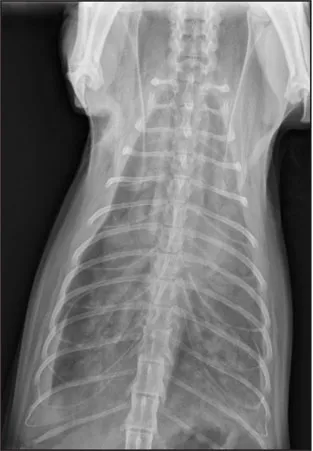

CASE 1.1 A 7-year-old neutered male Labrador Retriever who was hit by a car. You obtain these thoracic radiographs: Figs. 1.1a, b, left and right lateral projections, respectively; Figs. 1.1c, d, ventrodorsal and dorsoventral projections, respectively.

1.1a